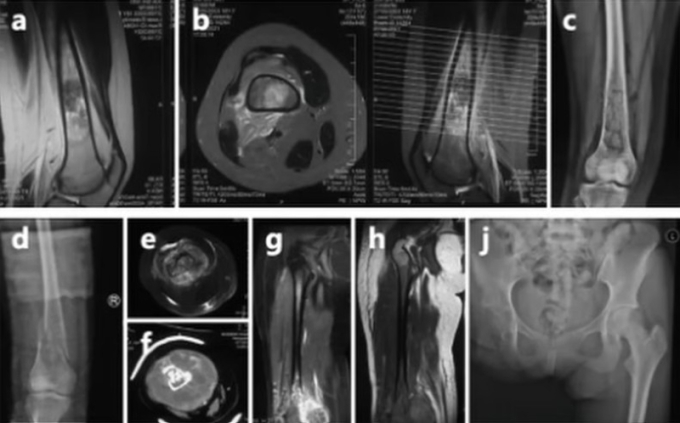

Phim chụp ung thư xương của Thế Vĩ. Ảnh: The Paper